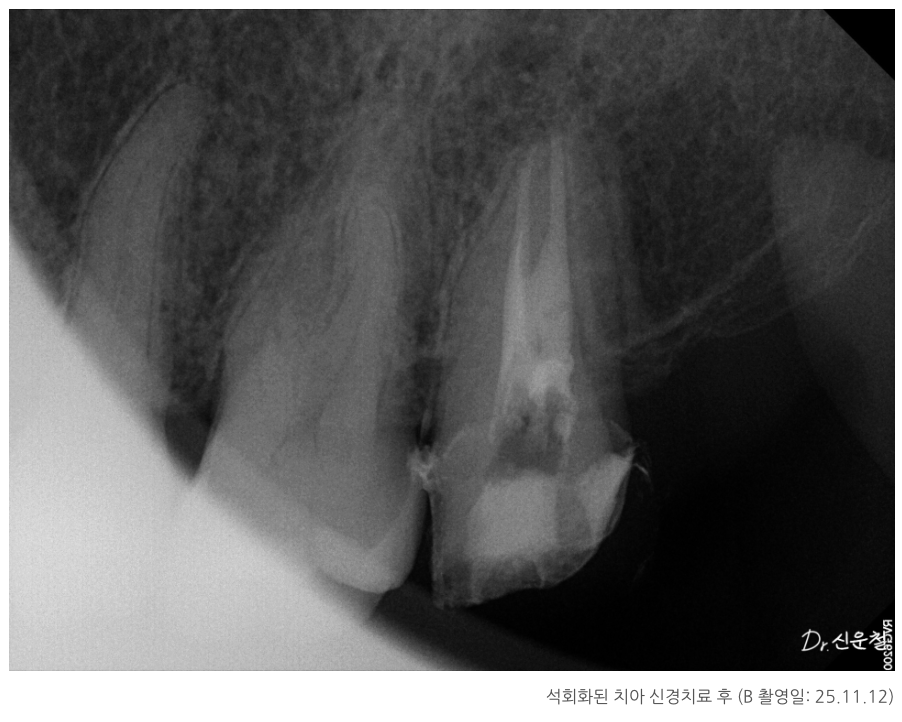

석회화된 치아, 정말 방법이 없을까?

실제 내원 사례 중에는

이미 신경치료를 받은 어금니에서

잇몸이 다시 붓고 고름이 차

발치 진단을 받고 오신 분도 계셨습니다.

또 다른 분은

“신경치료가 어렵다”는 설명을 듣고

의뢰로 내원하신 경우였습니다.

이 치아의 특징은 치아 안쪽 신경이 지나가는 길이

오랜 시간에 걸쳐 점점 막혀 있던 상태,

즉 석회화였습니다.

석회화란

원래 신경이 지나가야 할 공간이

시간이 지나면서 막히는 현상입니다.

방사선 사진에서 신경관이 잘 보이지 않거나

CT에서 신경이 있어야 할 자리가

빈 공간이 아닌 뼈처럼 보이는 경우가 이에 해당합니다.

겉으로 보면

“이제는 방법이 없는 치아”처럼 보일 수 있습니다.

치아 안쪽을 직접 확인하면서

남아 있는 길이 있는지

다시 정리가 가능한 상태인지 를 기준으로 판단했고, 그 결과

두 경우 모두 발치 대신 신경치료를 진행할 수 있었습니다.